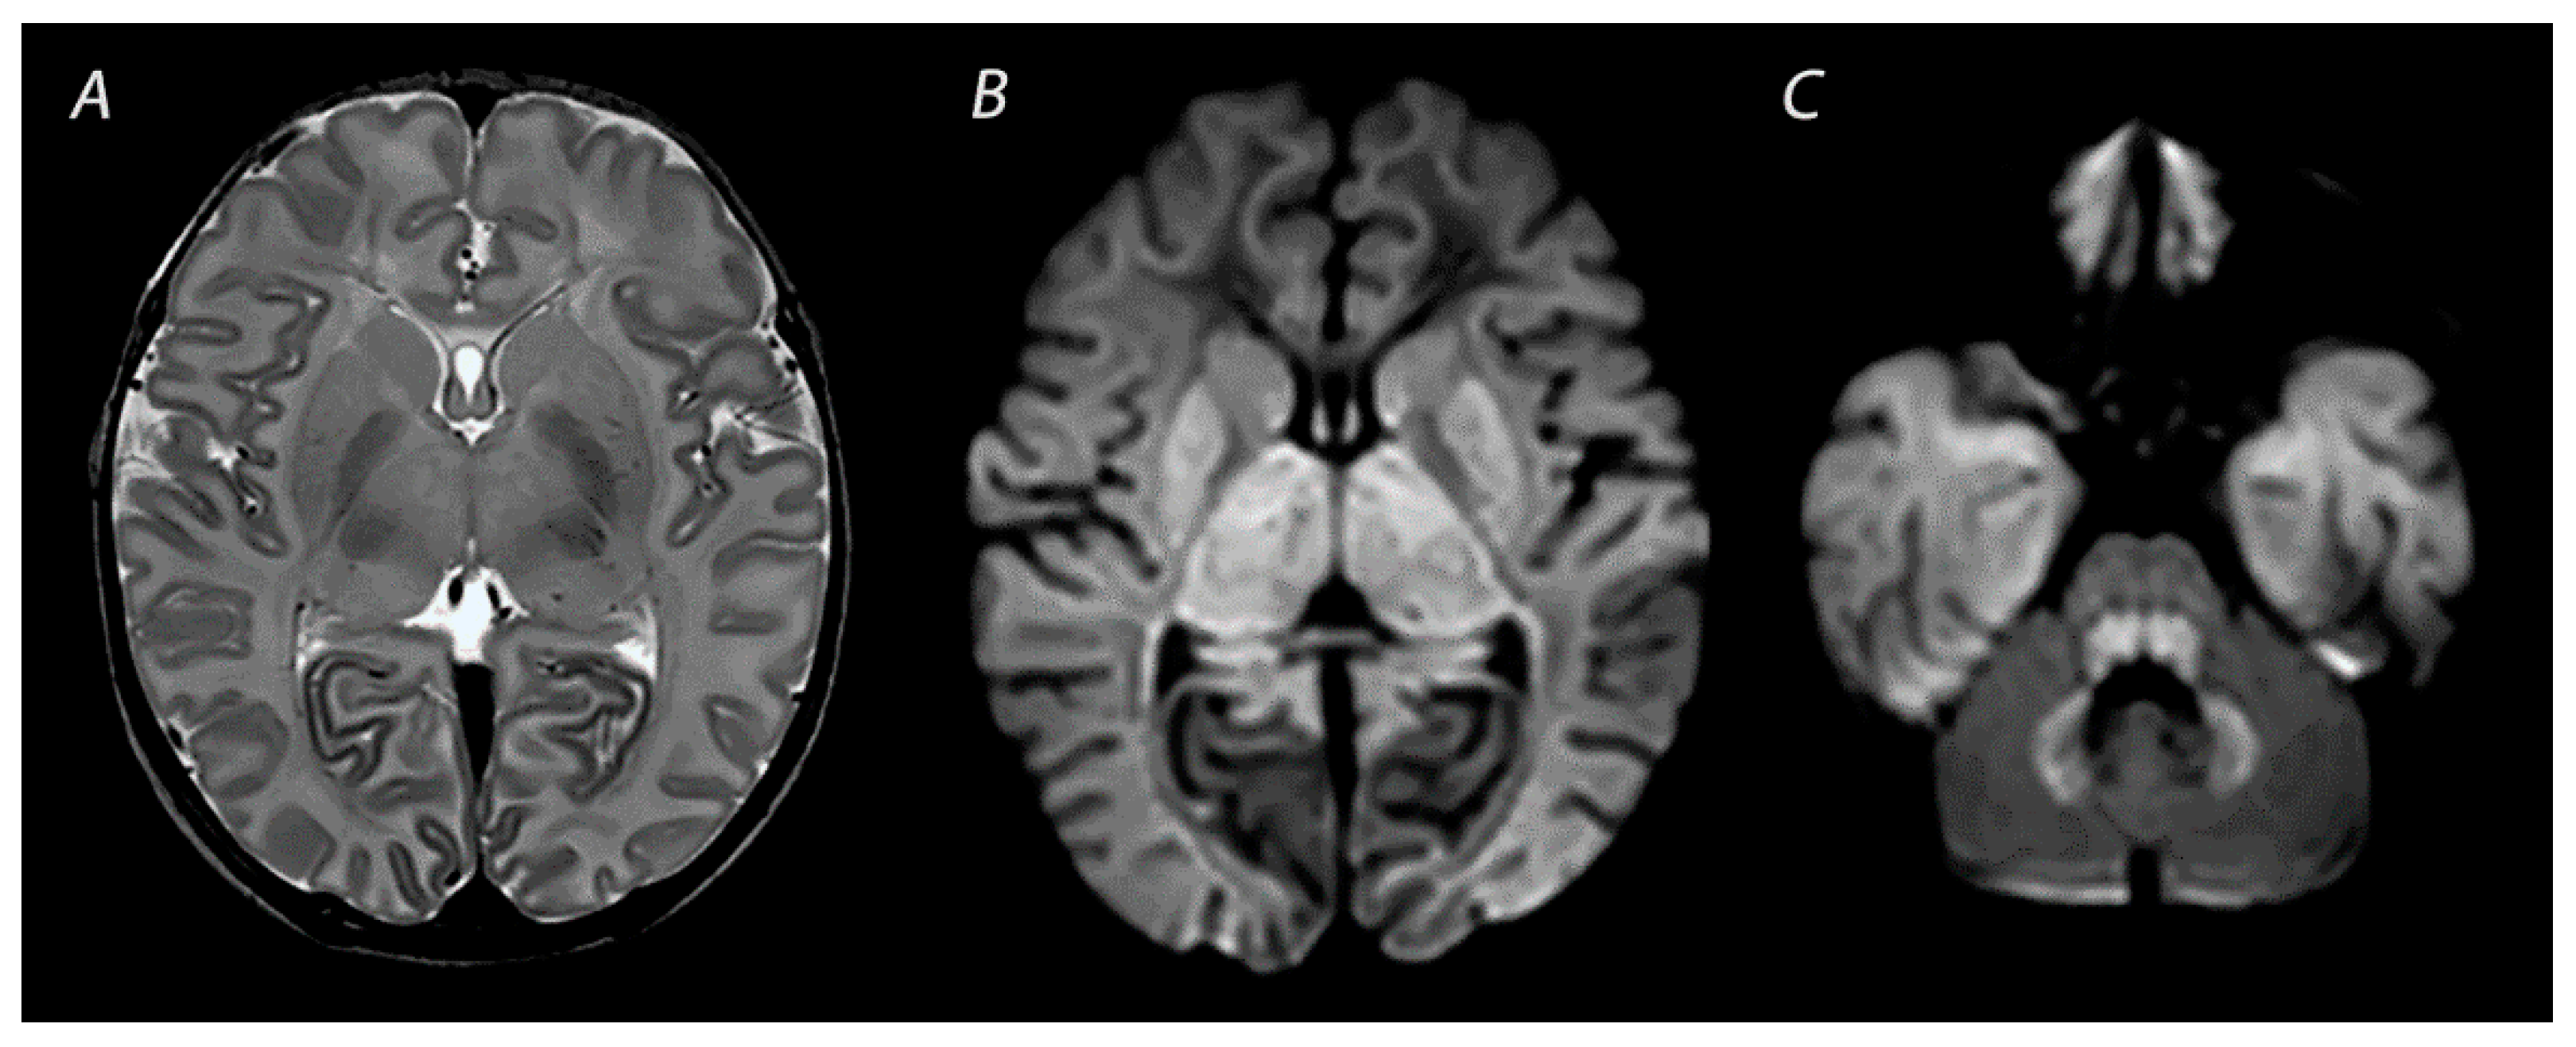

2.1. Basal Ganglia and Thalami (BGT) Predominant Pattern of Injury

| BGT | T1WI/T2WI | Abnormal signal intensity in the basal ganglia, thalami and the perirolandic cortex. Absence of a normal high-signal intensity of the PLIC. | Inconspicuous or subtle abnormalities in the first days, which become gradually more apparent by the latter half of the first week following the insult. MRI obtained beyond 1 month can show volume loss, cysts, gliosis and impaired myelination of the central gray matter and perirolandic cortex. |

| DWI | High signal intensity on isotropic DWI with low ADC values in affected areas. | Abnormalities peak at 3–5 days after the insult. Pseudo-normalization occurs after approximately 11–12 days for infants treated with therapeutic hypothermia, and 6–8 days in non-cooled infants. | |